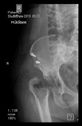

The guiding wire was inserted and controlled with fluoroscopy flashes (Figure 4). The drilling and reaming were carried out in accordance with the recommendations:

Figure 4.

The biocompatible aiming device after insertion of the guiding wire.

The direction of the cup stem was determined by the guide wire. The aiming device was needed to introduce this wire. After removing the aiming device, the next step was the drilling. Since a cannulated drill bit was used, the previously installed wire could guide the process. A self-positioning reaming tool was then used in the drilled channel. In the prepared cavity, the cup was fitted perfectly. Of the two stemmed cups available to us, the McMinn cup (Waldemar Link, Hamburg, Germany) had the simpler geometry and was therefore chosen. The stemmed cup was inserted according to the manufacturer’s recommendation. In the presence of a significant bone defect, a synthetic bone graft may be impacted for substitution.